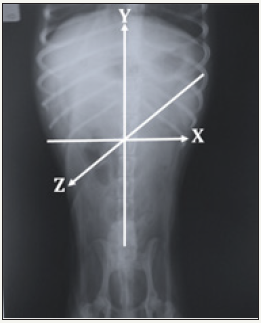

In a recent work of our research group [3], reference was made to the role that geometric thought plays in the imaginary mental configuration of histological structures, as well as their relationships, with the Cartesian coordinates X and Y coming into play, which for three-dimensionality the Z-axis is also considered. As already mentioned, the images obtained by X-rays are twodimensional shadows generated when projecting the X-ray beam to specimen. A three-dimensional mental configuration based on a system of axes is required, of the X, Y and Z coordinates represented in Figure 2, to obtain at least two orthogonal radiographs for threedimensionality. This way, the X axis goes from left to right, the Y axis from bottom to top and the Z axis from back to front [4]. Applying this in the abdominal cavity, in a lateral radiograph, Figure 3, the X axis would be long, from cranial to caudal, the Y axis would be wide, from ventral to dorsal, and the Z axis would be thickness from side to side of the cavity. Now, in a ventro-dorsal (VD) radiograph shown in Figure 4, the X axis is from side to side, the Y is caudal to cranial and the Z is from dorsal to ventral. Then, the positions are calculated by measuring the lateral position, height and depth for our spatial location.

Figure 2:X, Y and Z axis system.

Figure 4:X, Y, Z axis system applied to a VD abdominal radiograph.